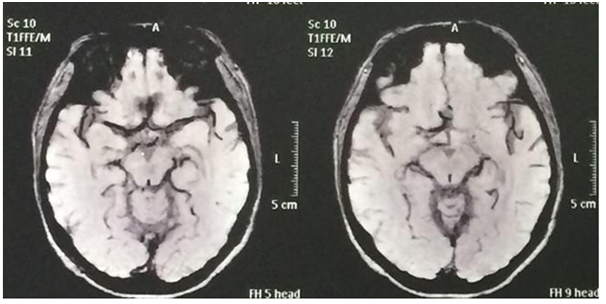

Female patient, 51 years old, brown, born in Juazeiro, Ceará. There was a month with progressive headache, pulsatile type in fronto-temporal region and right retro-ocular. In a few days, the right palpebral ptosis and hyperalgesia in V1 topography were added to the headache. Use of analgesics without clinical improvement ("the pain was so intense that she considered the possibility of suicide"). Absence of history of aneurysm and systemic diseases in the family. Deny contraceptive use. At physical examination: regular general condition, painful fascia, afebrile, atypical gait, eudychokinesis, right palpebral ptosis, as shown in Figure 1, consensual photoreagent, right mydriasis, as shown in Figure 2, hyperalgesia in V1 topography, strabismus divergent, as shown in Figure 3 & 4, and photophobia. Angiography confirmed the presence of sacculate aneurysm of the posterior communicating segment of the right internal carotid artery, as shown in Figure 5, also confirmed by magnetic resonance and magnetic resonance angiography, as shown in Figure 6 & 7. During the surgical procedure it was confirmed that the aneurysm dissected the cavernous sinus. However, it was observed that, instead of the lateral aneurysm in contact with the third cranial pair in the temporal, which is the habitual one, it made a medial orientation in contact with this in the cavernous sinus, due to the conformation of the aneurism in the form of hammer.6 This can also be justified by the fact that the posterior communicating artery in this case has no fetal pattern and the caliber of it is inferior to the posterior cerebral artery branch P1.6 In this way, it leaves the internal carotid artery in a more medial orientation.6 In the postoperative period there was an improvement in pain, but palpebral ptosis on the right, divergent strabismus, consensual photoreagent, fixed right mydriasis and photophobia persisted. Control angiography showed absence of residual aneurysm in the posterior communicating segment of the right internal carotid artery. Figure 8 shows the clipping of the region involved in the postoperative period.

Figure 7 Preoperative showing anatomical region of the cavernous sinus and right internal carotid Artery.